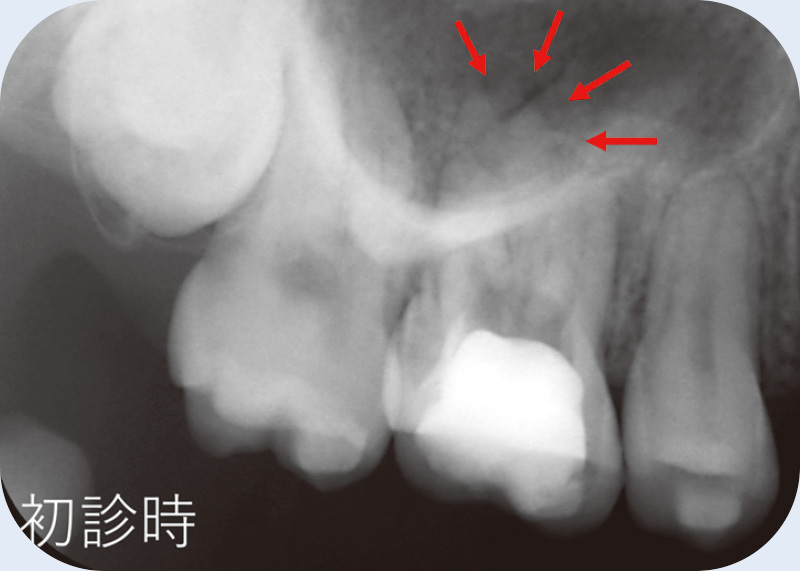

症例紹介① アクセスできない根管 富永 敏彦先生

![[写真] 術前](/academic/dentalmagazine/wp-content/uploads/sites/2/2025/11/195-3_photo02.jpg)

術前(Veraviewepocs 3Dにて撮影) -